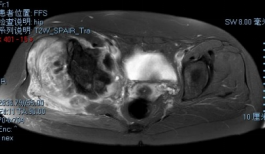

术前影像

穿刺活检提示骨盆软骨肉瘤

日前,安医大一附院骨病骨肿瘤外科胡勇教授团队成功完成一例复杂骨盆Ⅰ+Ⅱ+Ⅲ+Ⅳ区肿瘤切除与3D打印组配式半骨盆假体重建手术。患者为女性,53岁,下腰痛半年余,右侧臀部膨隆,右侧下肢轻度浮肿。右侧髂棘髂窝及臀部可触及巨大肿物,压痛明显,右髋外展前屈活动受限,右侧大腿感觉麻木,右足感觉运动正常。骨盆肿瘤切除重建是骨科专业中难度极大、风险极高的手术。骨盆肿瘤约占原发骨肿瘤的3%~4%,其中以软骨系统肿瘤最为多见,其次为骨巨细胞瘤、成骨肉瘤等,儿童尤文肉瘤亦好发于骨盆。

骨盆恶性肿瘤常潜在发展,由于骨盆位置较深,肿瘤早期很难发现,从第一次出现症状到诊断明确有时需要很长时间,当出现临床症状时,肿瘤体积已较大,因而手术切除相当困难。骨盆肿瘤血供丰富,手术出血多、难度大。另外,骨盆形态特殊,解剖复杂,切除肿瘤的同时,需要重建骨盆结构和肢体功能,技术要求高。